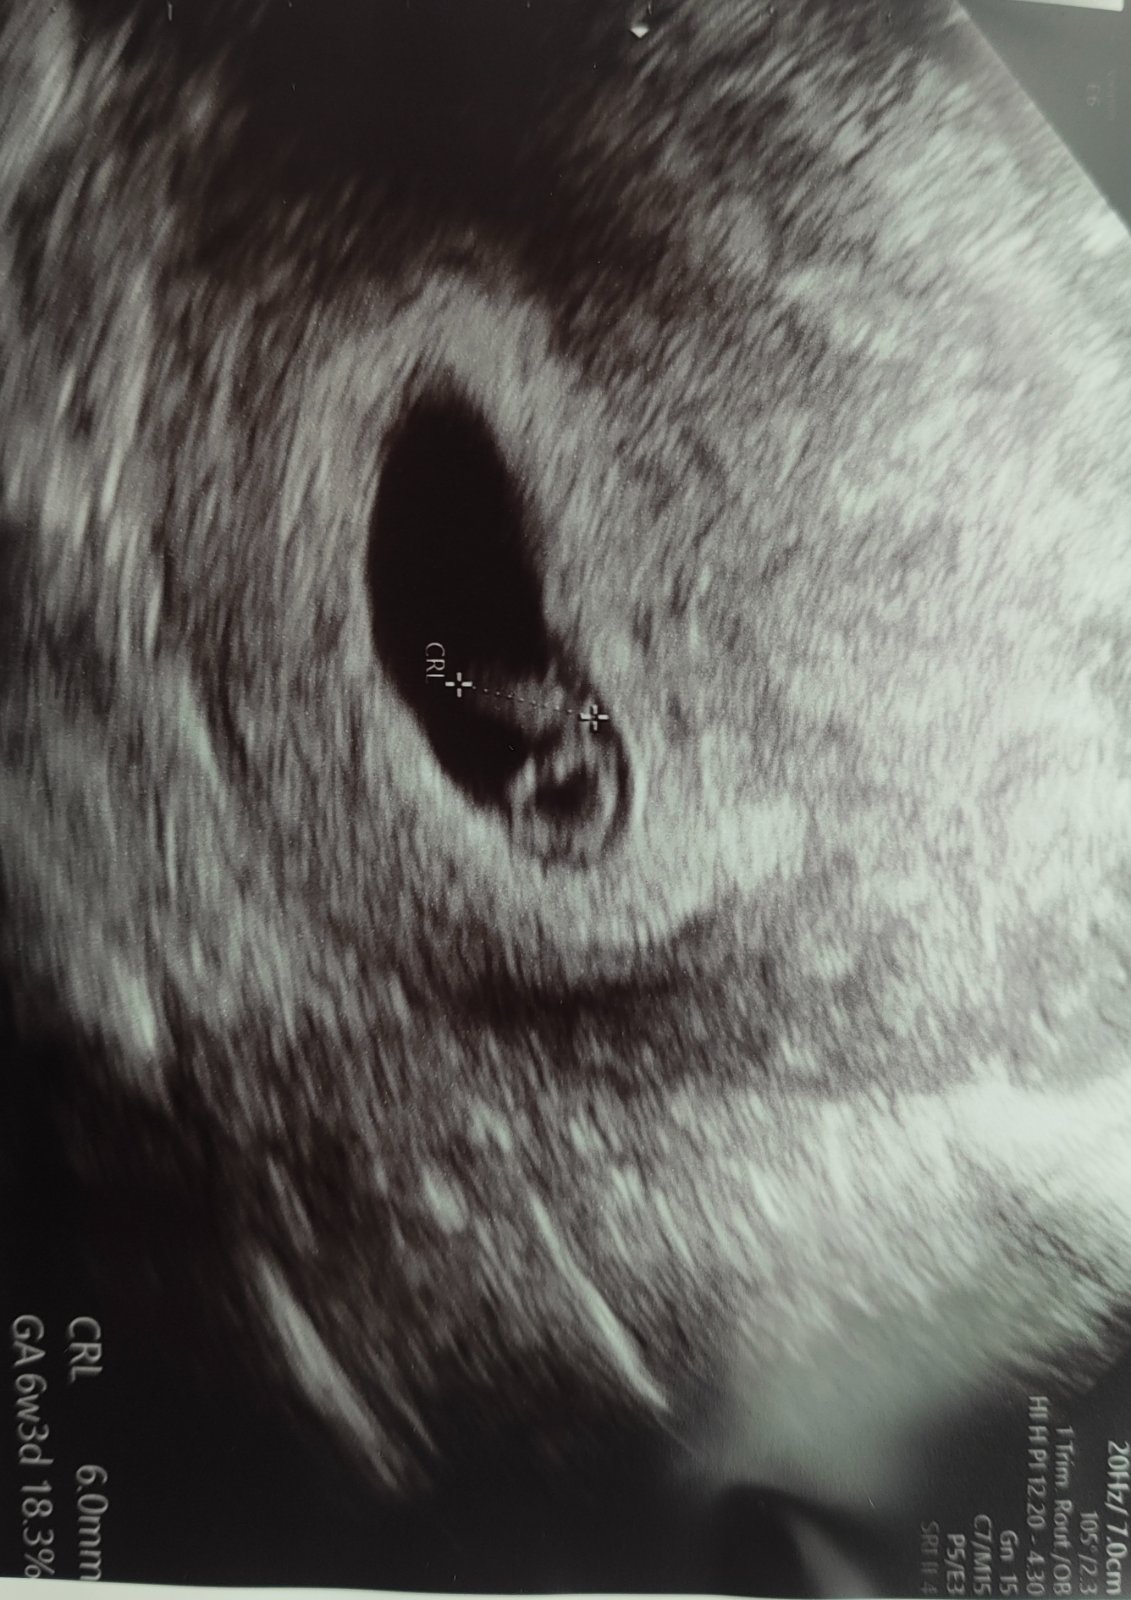

Ahojte, tak dnes som bola na SONE. Akcia ❤️ potvrdena, vsetko je tak ako ma byt. Velmi vam prajem, aby ste mali coskoro aj vy pozitivne informacie

Ahojte, ja som dnes 14dpt a mala som dnes krv aj sono a bolo už vidno malú bublinku.🙂 Pred hodinou mi volali z car a hcg mám 2552, kks mega😮💨 Len aby náhodou neboli namiesto jednej fazuľky dve🤣